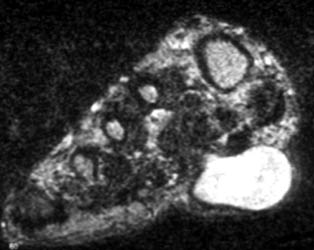

47 year old male with a 6 x 3.5 cm lobulated mass along plantar medial aspect of the 1st toe, which is hypointense on T1W and hyperintense On T2W images. Scattered small foci of hypointensity, representing calcifications is present on all the sequences. The soft tissue mass with small calcifications is also seen on the plain radiograph.